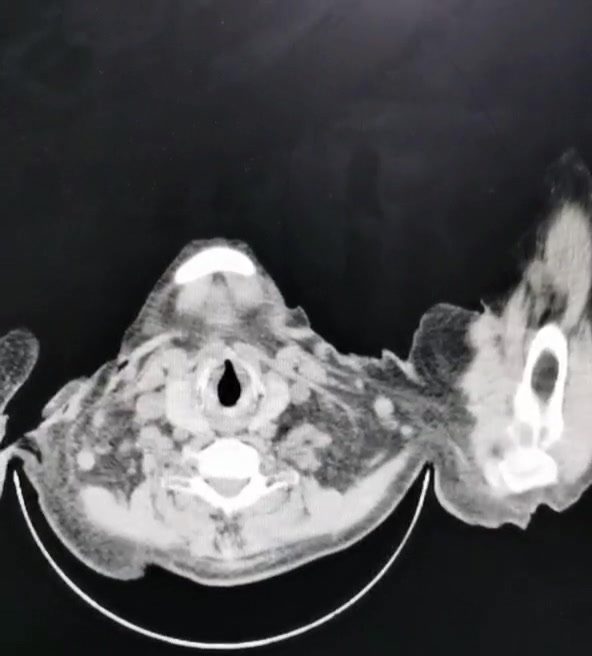

影像学检查:

⑥局部血管受压:下腔静脉、髂总静脉没有受压迫或者血栓情况,虽然CT看有囊肿,彩超也看了,支持囊肿;